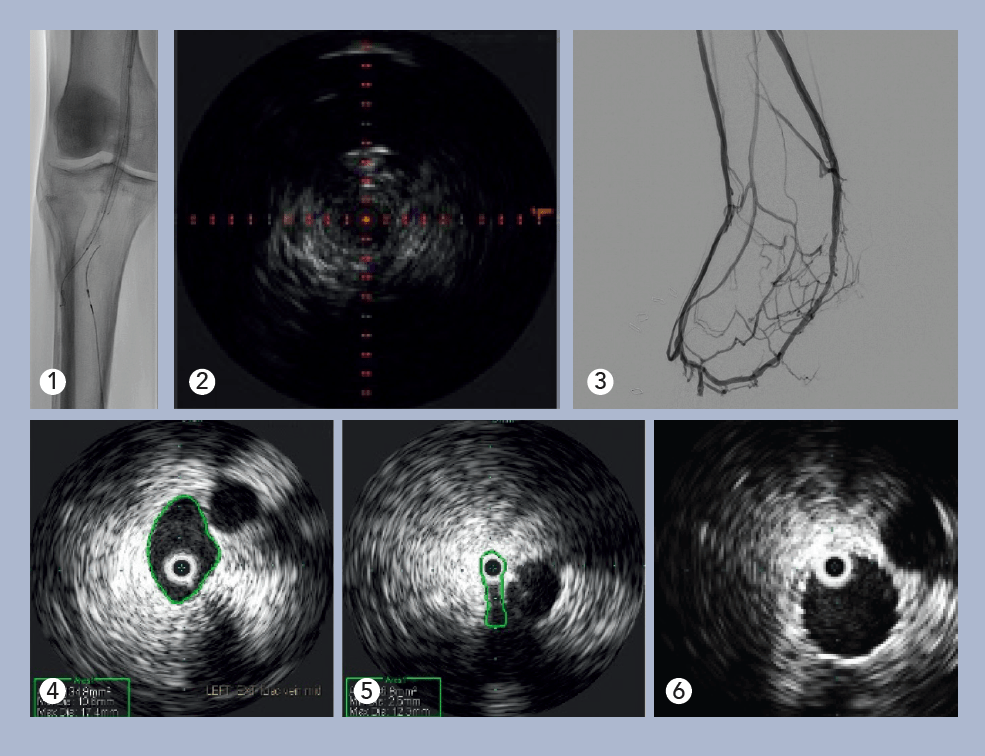

Deep venous arterialization (DVA) was performed using the Pioneer Plus catheter for IVUS-guided arterial re-entry (see Figure 1). Visualization of the popliteal artery re-entry target by IVUS allowed for rapid crossing from the posterior tibial venous access site (see Figure 2).

The use of covered self-expanding stents and percutaneous balloon angio-and venoplasty formalized the iatrogenic arteriovenous fistula. Post-intervention IVUS using the Reconnaissance .018 OTW IVUS catheter verified appropriate luminal gain and aided identification of incomplete venous valvular disruption in the foot (see Figure 3). Target areas of venous outflow were addressed with repeated venoplasty. At one-month follow-up, the patient reported marked symptomatic improvement, and non-invasive duplex imaging showed DVA patency.

Evaluation of the central veins in the pelvis with venogram revealed no focal iliac vein stenosis or filling defect, and there were no cross-pelvic or lumbar collaterals noted. IVUS with the Visions .035 system was performed, identifying a severe cranial external iliac vein (EIV) stenosis (73%), compared to the normal suprainguinal caudal EIV, due to a non-thrombotic iliac vein lesion (NIVL). Normal suprainguinal caudal EIV and severe cranial external iliac vein stenosis (see Figures 4 and 5).

Post-angioplasty and stent, there was no residual stenosis (Figure 6). On follow-up exam one week later, the stent was widely patent on duplex ultrasound, and the patient remarked, “I can see my ankle again!”